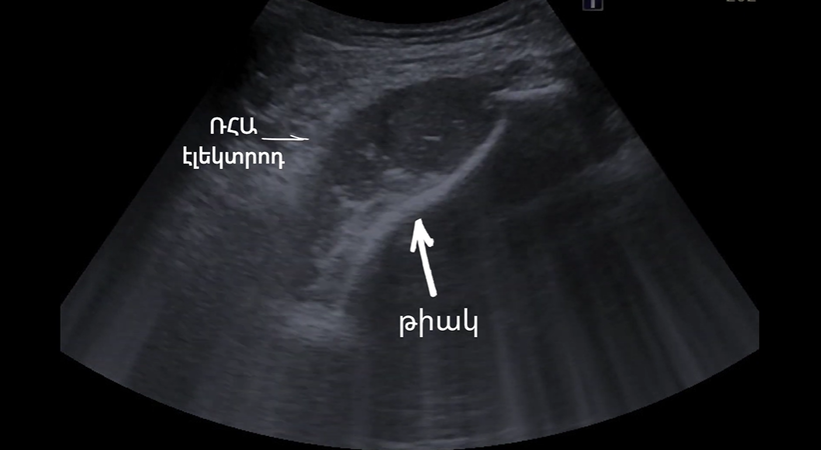

Home Photos Bone tumor radiofrequency ablation Blog Bone tumor radiofrequency ablation Radiofrequency ablation of hepatic metastatic disease using advanced interventional radiology techniques. Percutaneous radiofrequency ablation of a metastatic lesion in the scapular region under ultrasound guidance. Excisional biopsy of a lymph node at the Interventional Radiology Service. For the first time in Armenia, a transjugular intrahepatic portosystemic shunt (TIPS) has been performed. Thyroid nodule ablation Embolization of an intraductal tumor Intrahepatic Tumor Biopsy